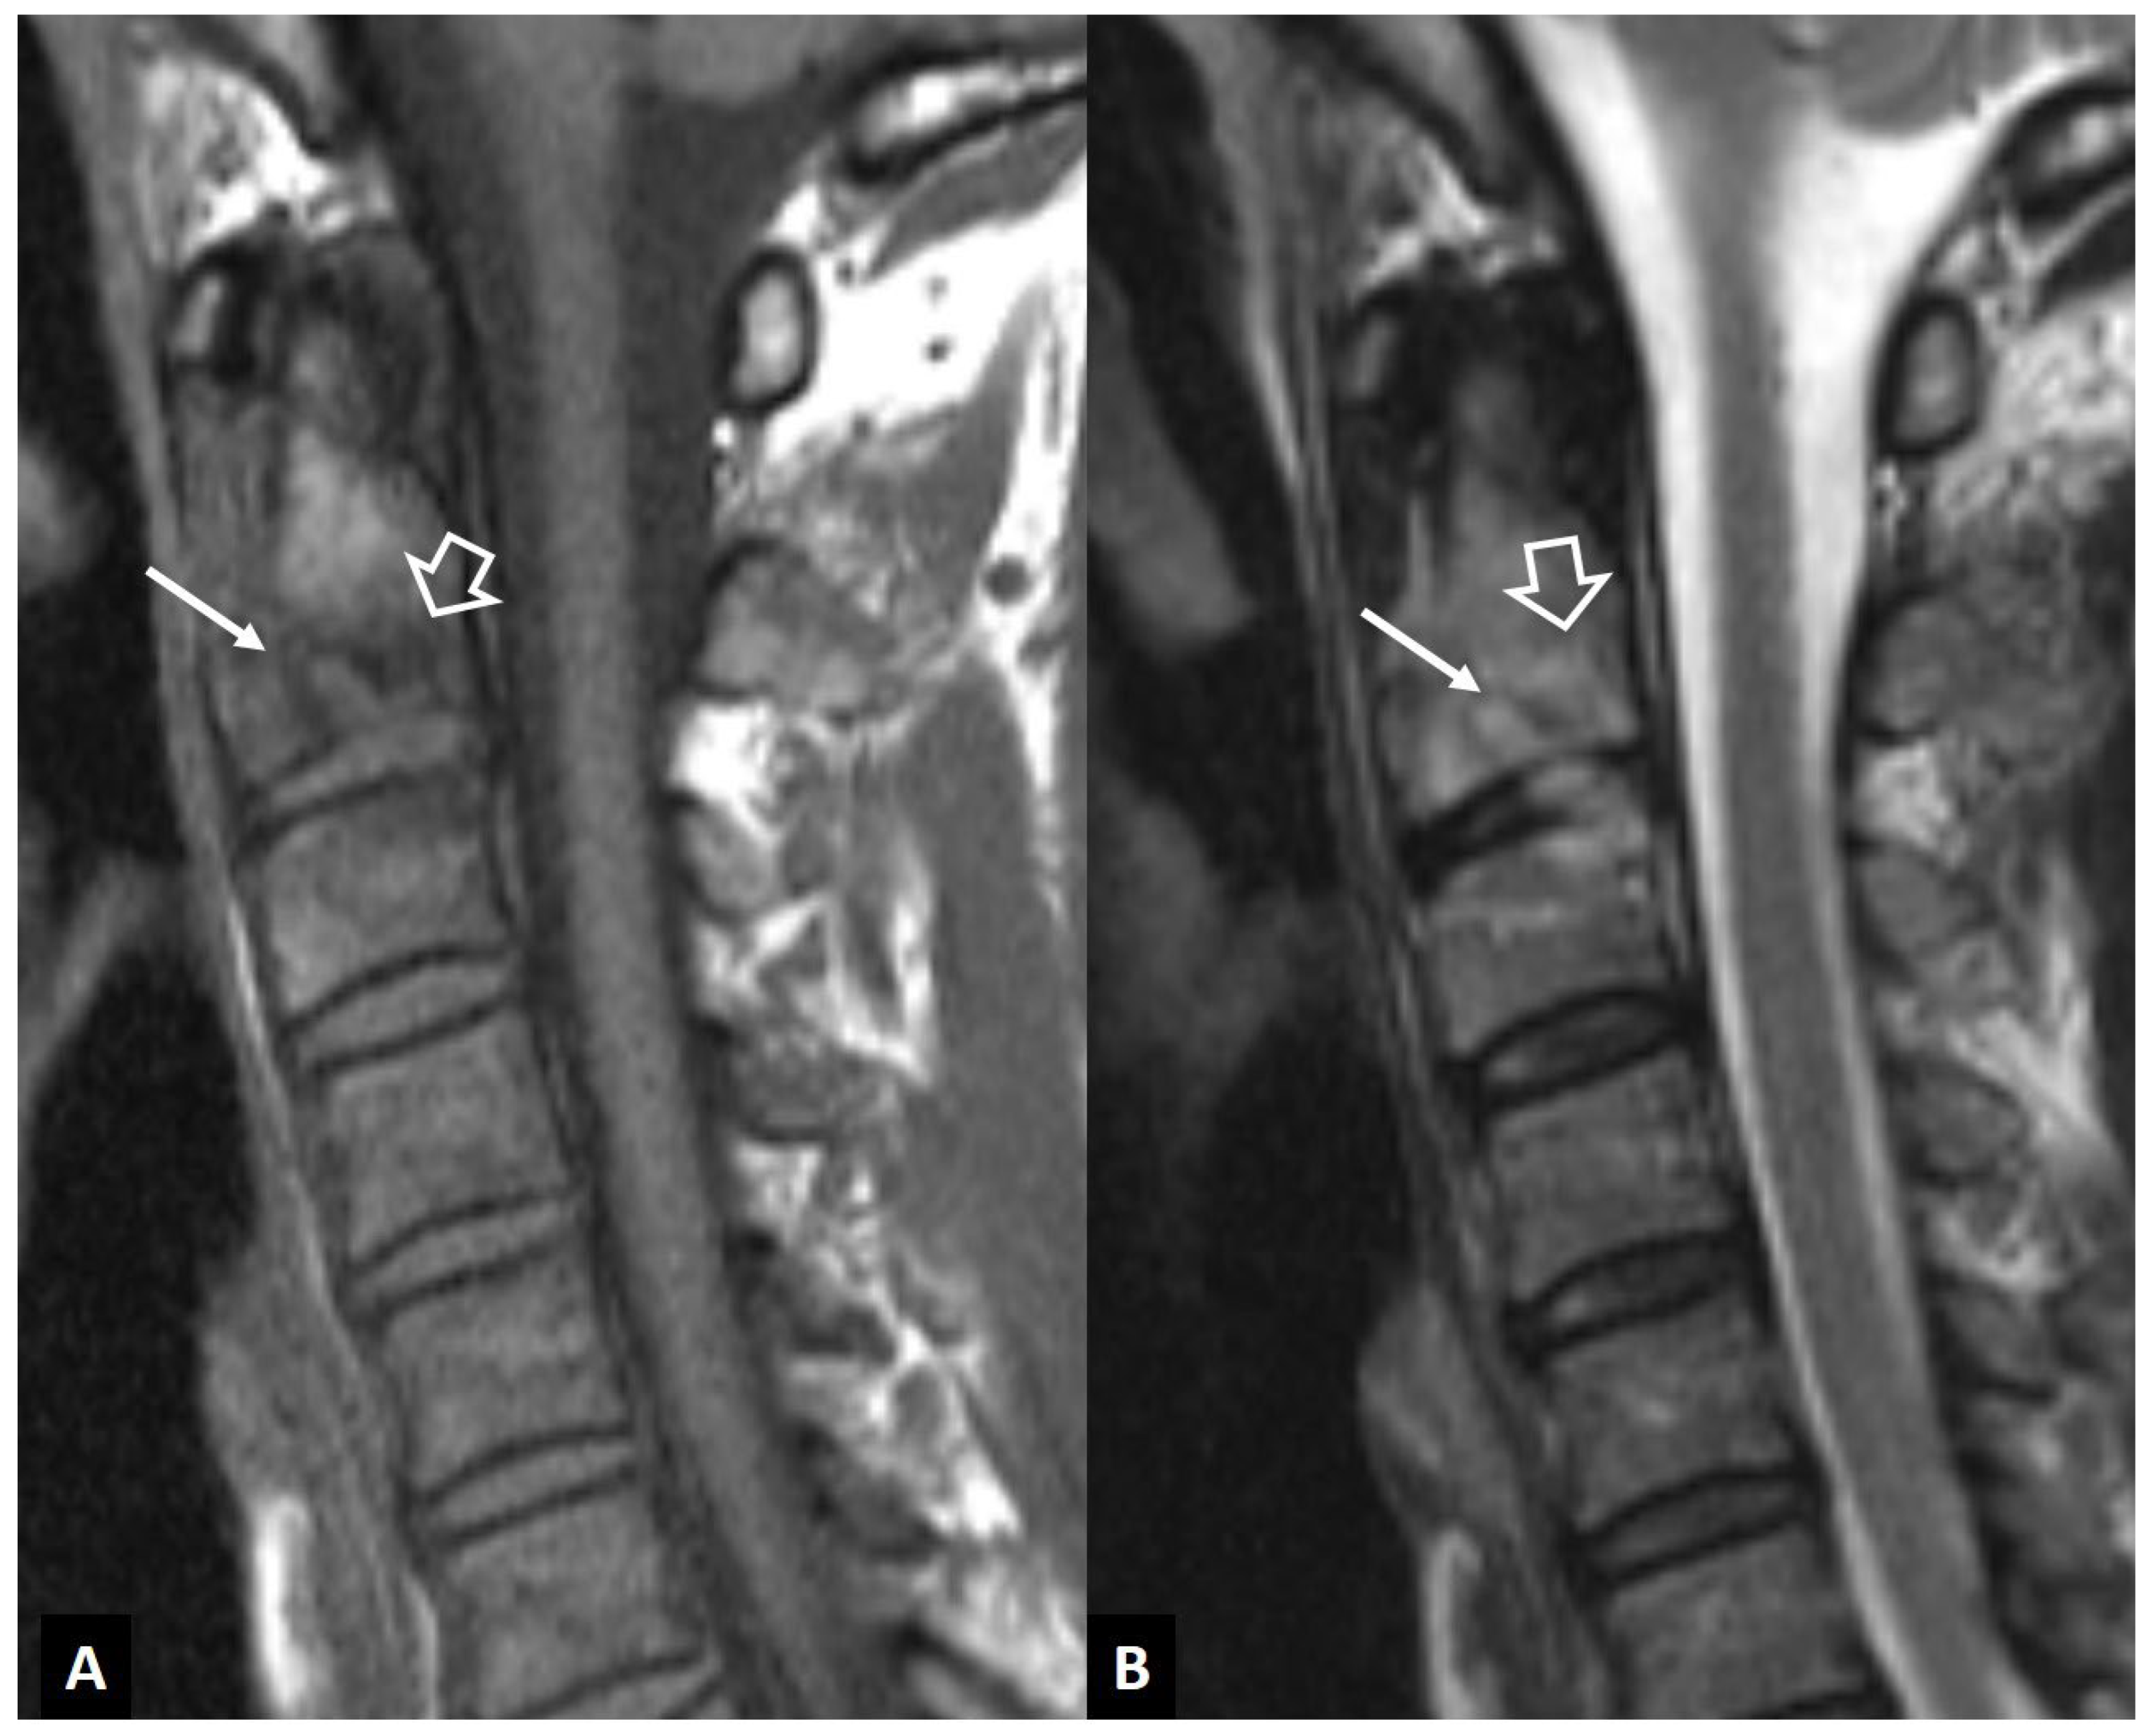

1. a.viii. Rheumatoid Arthritis

1. b. Non Infectious Sacroiliitis